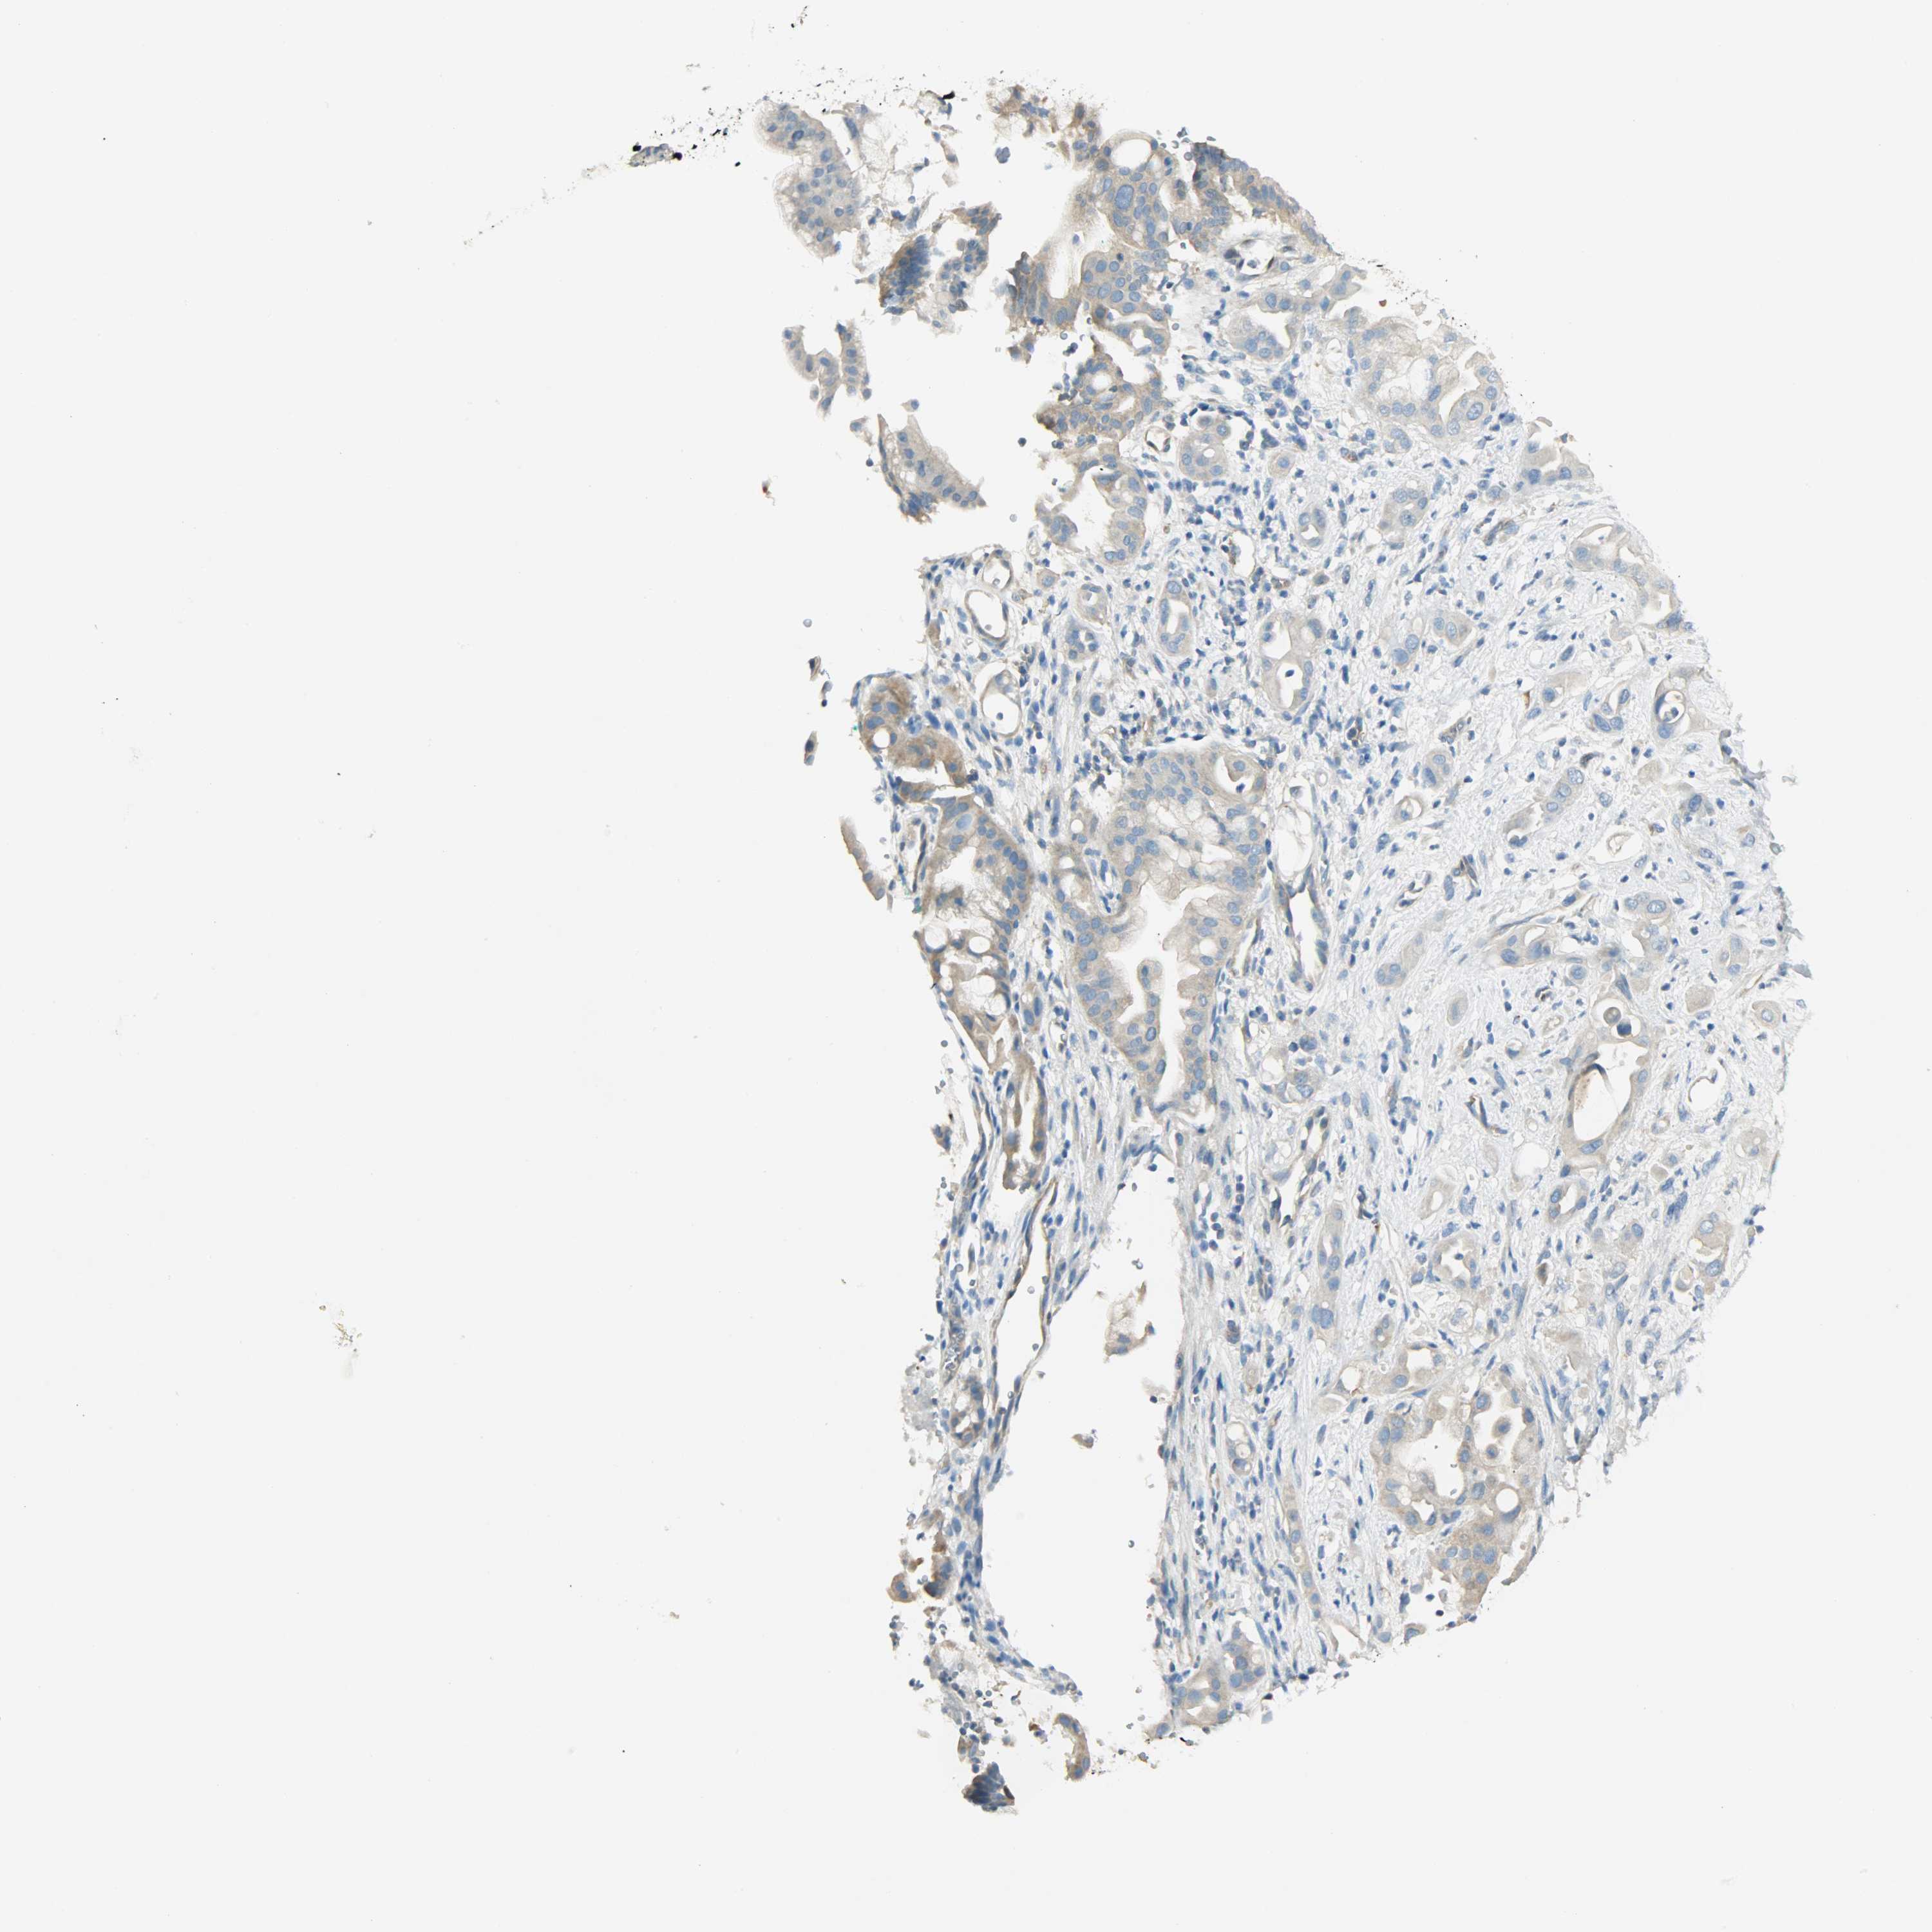

PANCREATIC CANCER - Protein expressioni

A mouse-over function shows sample information and annotation data. Click on an image to view it in a full screen mode. Samples can be filtered based on level of antibody staining by selecting one or several of the following categories: high, medium, low and not detected. The assay and annotation is described here.

Note that samples used for immunohistochemistry by the Human Protein Atlas do not correspond to samples in the TCGA dataset.

Antibody stainingi

Antibody staining in the annotated cell types in the current human tissue is reported as not detected, low, medium, or high, based on conventional immunohistochemistry profiling in selected tissues. This score is based on the combination of the staining intensity and fraction of stained cells.

Each image is clickable and will lead to virtual microscopy that enables deeper exploration of all samples and also displays staining intensity scores, fraction scores and subcellular localization as well as patient and tissue information for each sample.

Antibody HPA004926

Staining

High

Medium

Low

Not detected

Intensity

Strong

Moderate

Weak

Negative

Quantity

>75%

75%-25%

<25%

None

Location

Nuclear

Cytoplasmic/membranous

Cytoplasmic/membranous,nuclear

Adenocarcinoma, NOS

Adenocarcinoma, metastatic, NOS